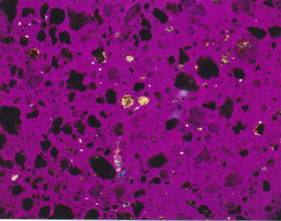

Pseudoizotropní agregáty apatitu se

stopami Whewellitu.

Zrnkový preparát, polarizační mikroskop, zvětšeno 160x